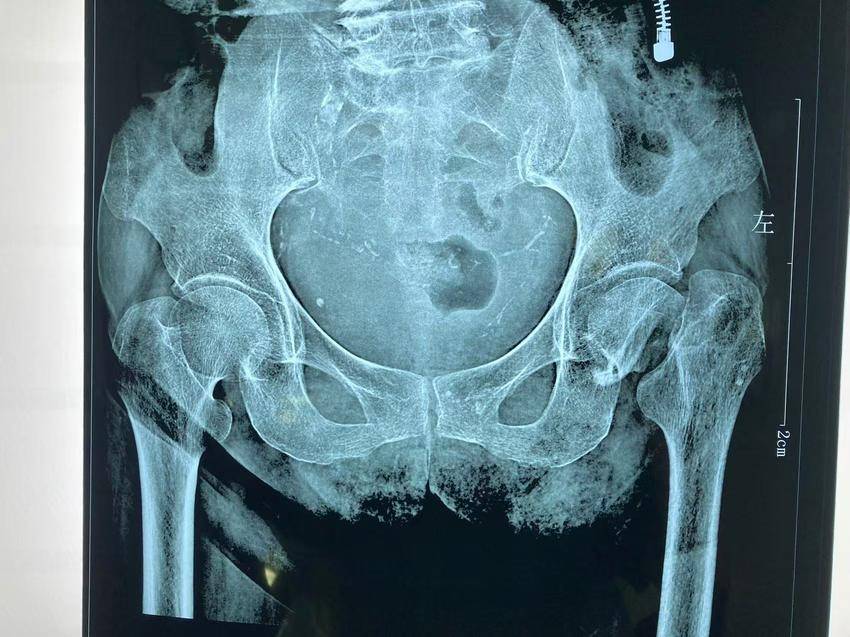

半月前,在家摔伤两月余的罗婆婆被家属送至县二院外一科。检查发现,罗婆婆左股骨颈骨折已有两月余,同时患有急性心力衰竭、心律失常、心包积液,科室给予强心、利尿、营养心肌、预防深静脉血栓、下肢牵引等治疗,治疗两周后,罗婆婆血压、心率降至正常;双下肢凹陷性水肿消退;心脏功能也大有好转。